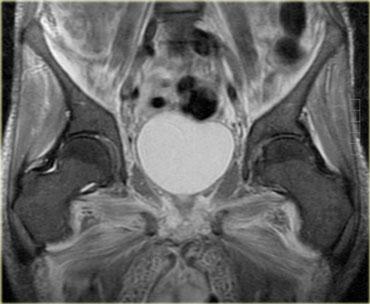

Ví dụ, như ở bệnh nhân SLE này, tổn thương có thể rất khu trú (ảnh mặt phẳng coronal, chân phải, khoang cơ khép) hoặc dạng nốt.

Một dạng viêm cơ nốt là viêm cơ tăng sinh khu trú, đây là thể ít gặp nhất.

Dạng này có thể gặp không chỉ trong bệnh mạch máu collagen mà còn trong u lympho.

Tổn thương do viêm cơ đôi khi không thể phân biệt được với bản thân u lympho, và cần sinh thiết để xác định chẩn đoán.

Hình bên trái là một bệnh nhân khác với viêm cơ nốt khu trú, trông giống như bất kỳ khối nào khác trên chuỗi xung T1W, T2W và sau tiêm thuốc tương phản từ.

Với tiền sử u lympho, có thể gợi ý viêm cơ nốt khu trú, nhưng không có gì mang tính quyết định từ các hình ảnh này.

Mối liên hệ giữa viêm cơ và bệnh ác tính tiềm ẩn vẫn còn gây tranh cãi, và tần suất của mối liên hệ này chưa được xác định rõ ràng.

2 loại ung thư có mối liên hệ với viêm cơ: ung thư buồng trứng và u lympho không Hodgkin

(hình bên trái là bệnh nhân với, thật kỳ lạ, ung thư tuyến giáp di căn).

Viêm cơ có thể xuất hiện trước bệnh ác tính (như trong hội chứng cận u), điều này không có nghĩa là cần tầm soát ác tính thường quy

ở bệnh nhân biểu hiện viêm cơ.